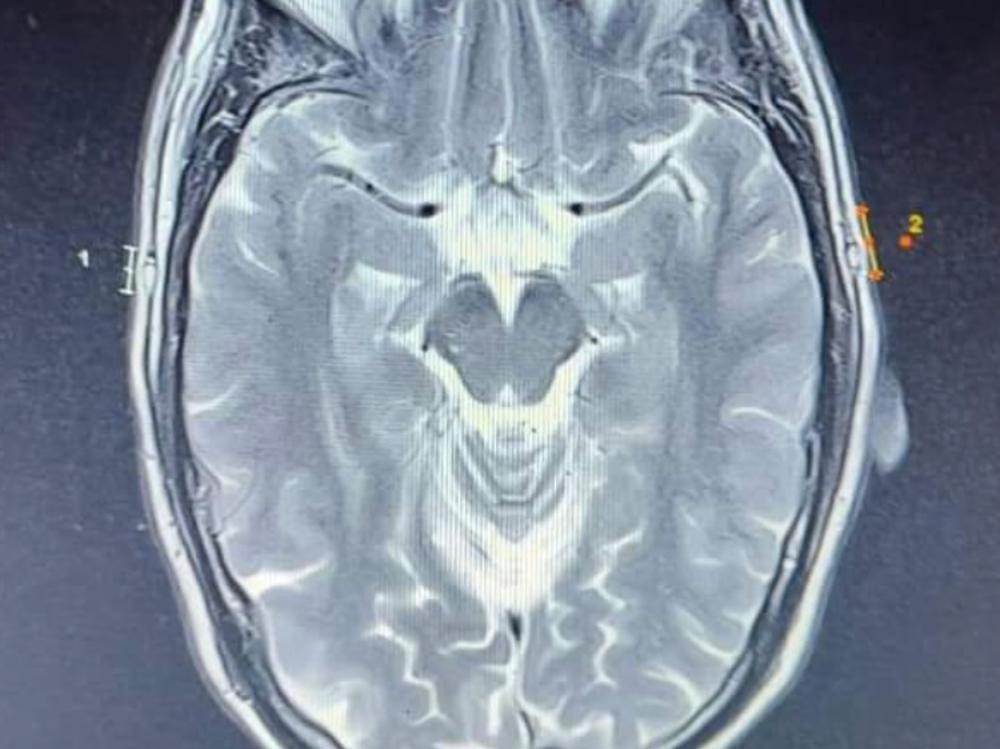

I am looking for assistance to get an MRI and see a specialist due to being in severe pain and constant loud high pitch noises in my head.

For around the last decade I have been very unwell. I have been in severe pain, the left side of my head is in continuous pain, my brain feels like someone is rubbing fine sand paper on it and I have the loudest high pitched 24/7 cricket like sound, mainly on the left side of my head. I also have severe insomnia, v2k like sounds and I am having cognitive problems and memory problems. While we have medical care in New Zealand, it doesn’t cover me getting an MRI and other scans, consulting specialists etc which I am in need of. I have no money after having having to leave my job many years ago and just want the torture to stop.

Brain MRI, Full MRI, seeing a specialist in neurology, buying equipment to help find out and monitor EEG brain signals.